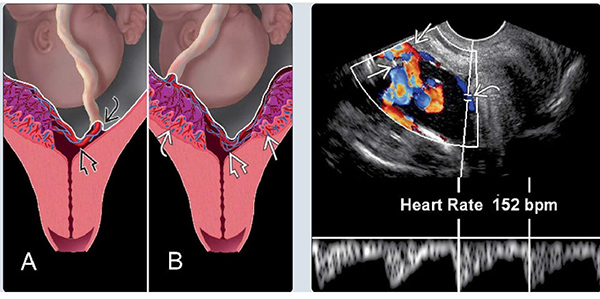

Lúc này bác sĩ sẽ sử dụng phương pháp siêu âm đầu dò kết hợp với siêu âm Doppler để chẩn đoán sớm và đưa ra các biện pháp điều trị kịp thời. Thực chất thì những thai phụ được chẩn đoán có nhau cài răng hoặc thuộc nhóm đối tượng có nguy cơ cao sẽ được tiến hành xét nghiệm.